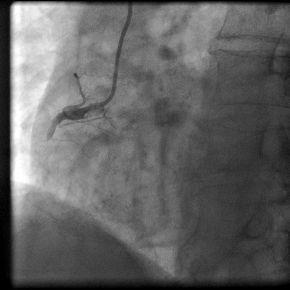

病例介绍:陈姓35岁青年男性,因“突发胸痛2小时”与凌晨1:00入我院急诊科,入院后即刻心电图提示急性下壁、后壁心肌梗死,认为应立即行急诊PCI术。立即给予足量阿斯匹林和波立维,启动急性心肌梗死救治绿色通道。导管室护士、技师、心内科医生在导管室等待,并且做好术前准备。在得到患者家属同意后,我们迅速带患者入导管室。急诊冠脉造影示:右冠状动脉近段完全闭塞,通过血栓抽吸,球囊扩张,开通闭塞血管,右冠近段成功植入药物涂层支架一枚,患者转危为安,整个过程用时28分钟。